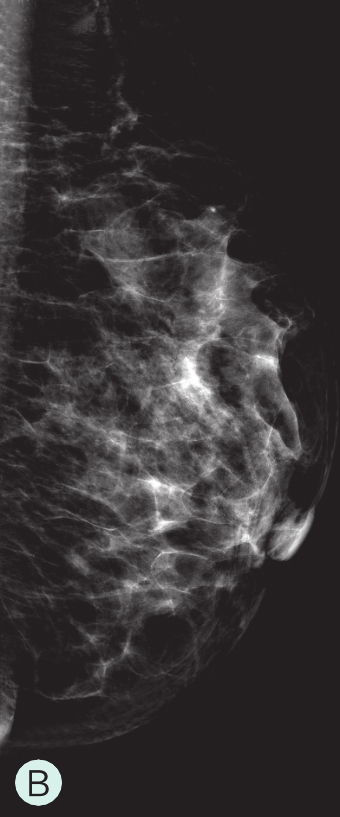

图1-3-2 乳腺超声不同乳腺密度

A.脂肪型;B.散在致密型;C.不均匀致密型;D.极度致密型

B级:散在纤维腺体致密型(图1-3-1B、图1-3-2B、图1-3-3B)。